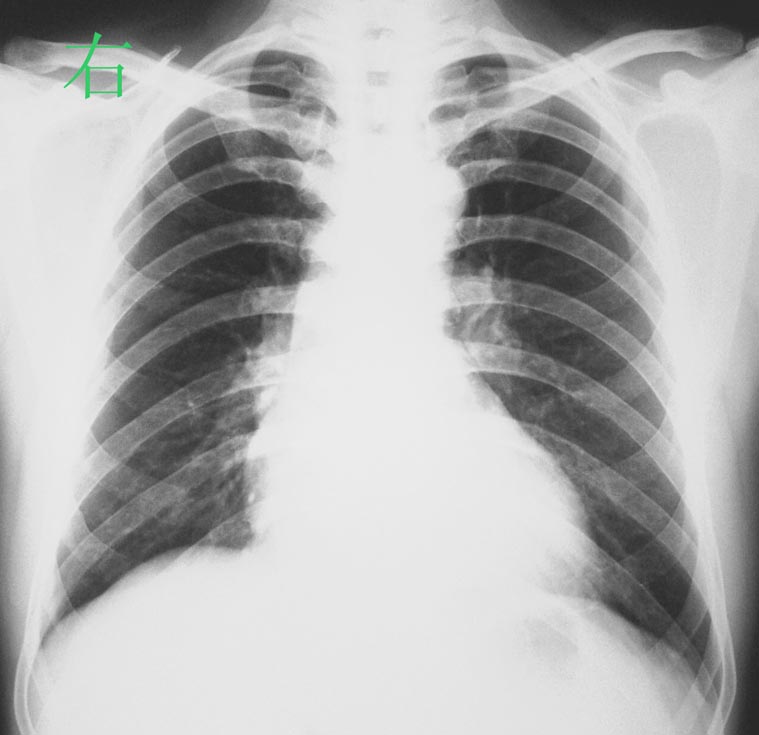

标题: 回复:x0288:随访图片

患者经抗炎治疗后一周+图片,病灶明显吸收.

患者抗炎治疗后三周图片,病灶已基本吸收.